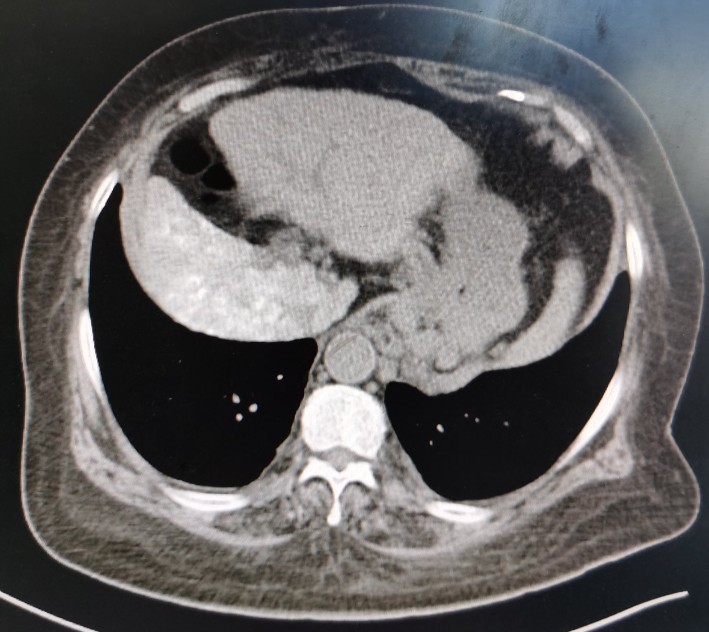

肝脏

正常肝脏CT片